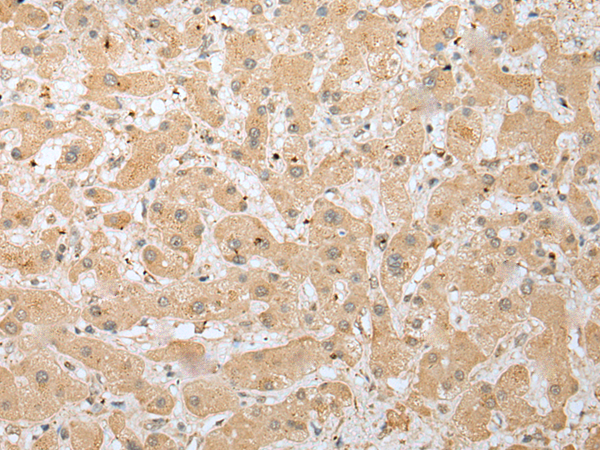

IHC positive control: |

Human liver cancer and Human lung cancer |